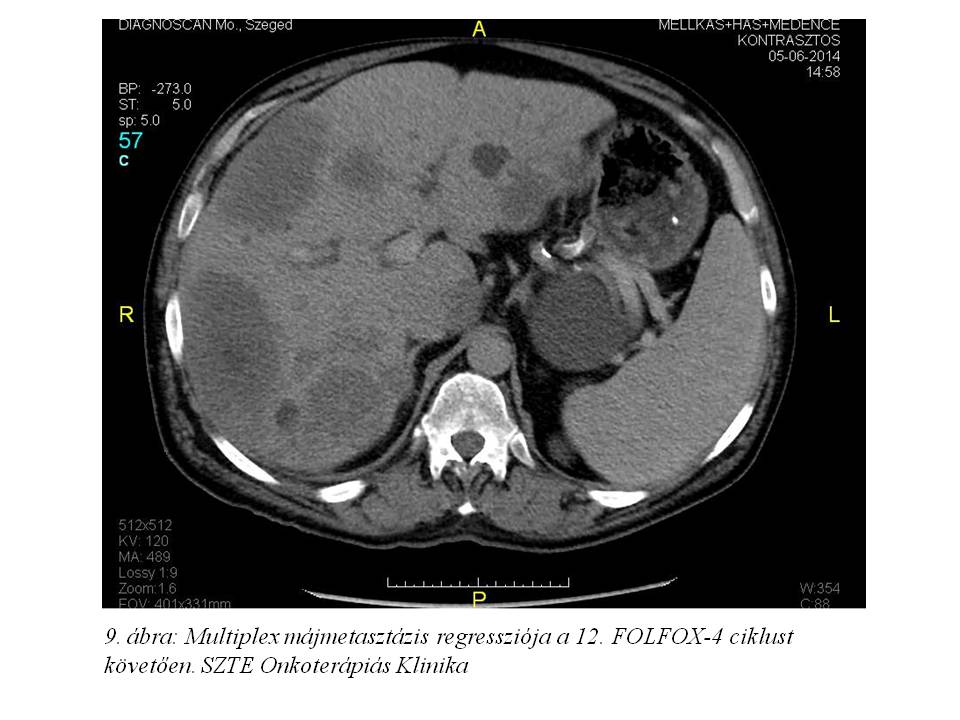

A 12. ciklust követő soros re-staging has-kismedence CT-n további regressziót láttunk (2014.06.05., 9. ábra), a mellkas CT-n tüdőmetasztázis nem volt azonosítható; a CA 19-9 és CEA normál értékű. A mellékhatásként kialakult perifériás sensoros neuropathia fokozódott, zsibbadás kezdődött, de a mindennapi teendőkben még nem zavarja. Az oxaliplatin dózisában 2. szintű redukciót alkalmaztunk (65 mg/m2).